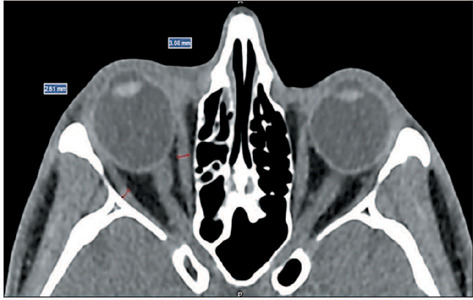

Objective: To assess the prevalence of changes on computed tomography (CT) in Graves' orbitopathy (GO) and to correlate those changes with disease activity, as well as with clinical and biochemical variables.

Materials and methods: This was a retrospective study, conducted at a tertiary hospital, of clinical, biochemical, and imaging data from consecutive patients with GO who underwent at least one orbital CT scan between July 2012 and December 2020. A single observer quantified the thickness of the extraocular muscles and the degree of proptosis. Clinical and biochemical variables were analyzed to determine whether they correlated with CT changes, GO activity, and GO severity.

Results: Our sample included data from 67 patients with GO (134 orbits), 50 (74.6%) of whom were female. There were positive correlations between the clinical activity score and increase in thyroid-stimulating factor/free thyroxine, between the severity of GO and the increase in the thickness of the extraocular muscles, and between the degree of proptosis and muscle thickness.

Conclusion: Orbital CT proved effective in detecting thickening of the extraocular muscles and proptosis in patients with GO, changes that correlated significantly with clinical and biochemical variables. Muscle thickening was associated with the severity of GO and could be a biomarker of the risk of vision loss.